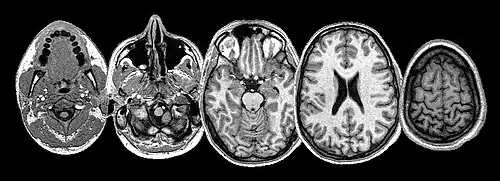

An MRI scan of a human head.